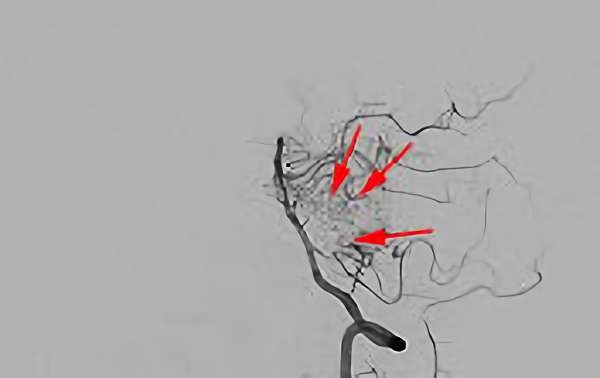

No.1620 手術前

No.1620 手術中

No.1620 手術後